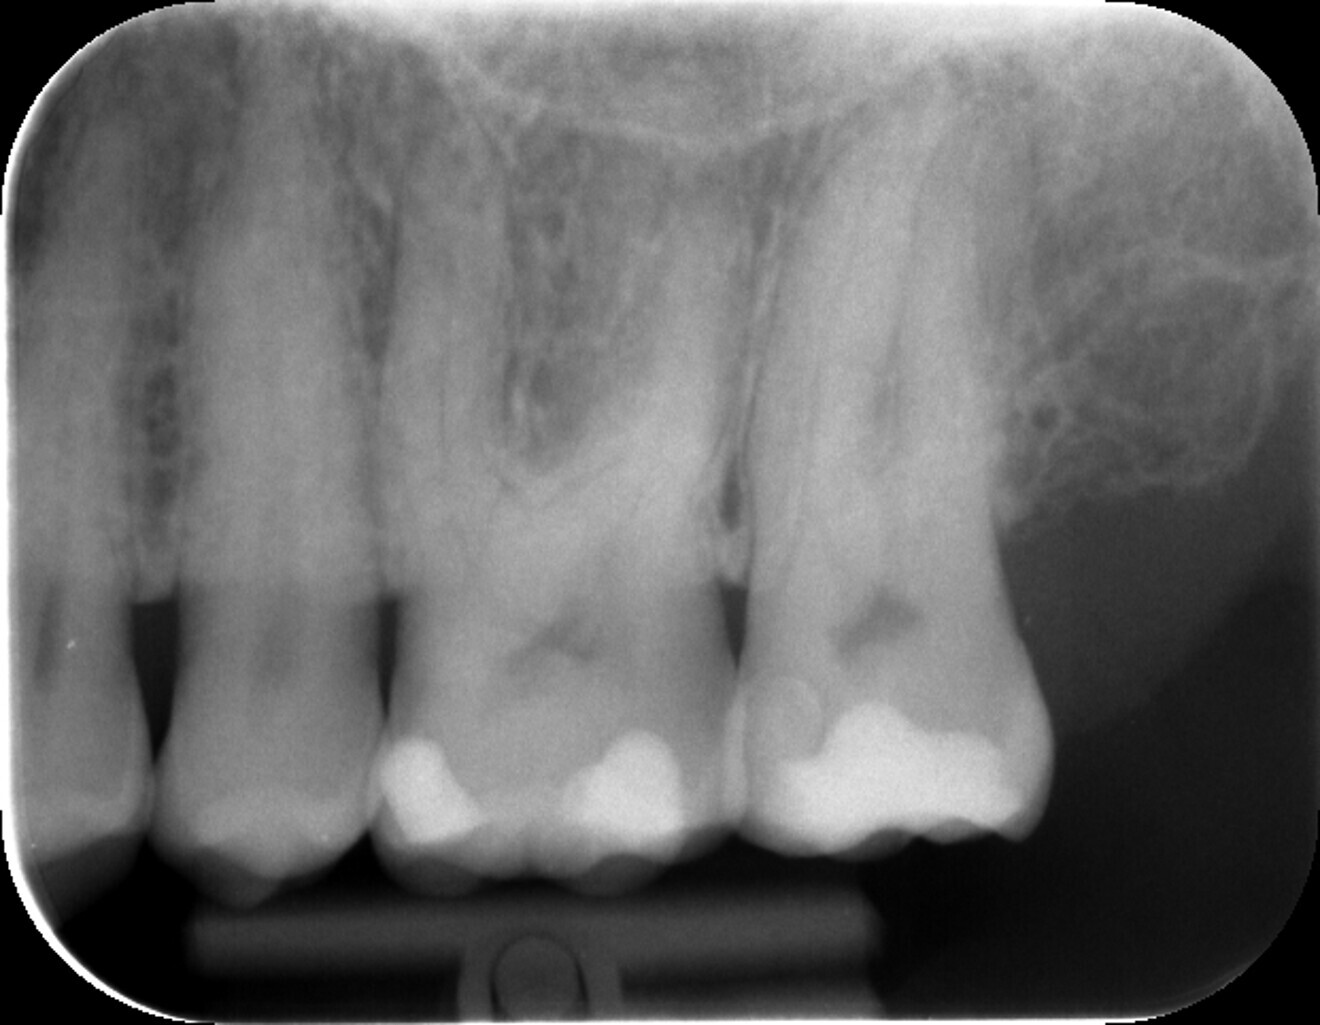

The user-friendly endodontic motor CanalPro X-Move (COLTENE) and the HyFlex EDM instruments in the OGSF sequence (COLTENE; Fig. 4) were chosen for straightforward preparation. The abbreviation “OGSF” stands for the first letters of the four NiTi files, which can be used to treat the majority of typical endodontic cases quickly and conveniently: the Opener (orifice opener) opens the tooth to be treated, the Glider (glide path file) helps to create a glide path which follows the natural contour of the canal, the Shaper (shaping file) efficiently removes bacteria and infected tissue and creates the prerequisites for the canal obturation, and the Finisher (finishing file) ensures that the apical area is sufficiently cleaned and that there is sufficient space for irrigating solutions to reach the apex.

The well-organised set of four coordinated special files with matching gutta-percha points offered the great advantage that no individual files had to be preselected ahead of treatment. The prebent files moved safely in the centre of the canal, making handling extremely smooth. Furthermore, the files are highly resistant to breakage, and this ultimately benefits both the patient and the practitioner.